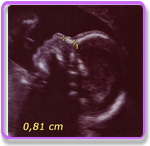

Das sogenannte Ersttrimester-Serumscreening (PAPP-A, freies ß HCG-10+3 bis 13+6 SSW) und die Messung der Nackentransparenz (nuchal translucency)(Nt-Messung) ergibt eine statistische Sicherheit von 90%! noninvasiv! (Ein sicherer Ausschluss von Chromosomenstörungen ist nur durch eine genetische Untersuchung aus Fruchtwasser oder Plazentagewebe  möglich; also dann aber invasiv.)

Nt-Messung: Im Ultraschall können wir ab der 11+0 bis zur 13+6 `ten Schwangerschaftswoche im Nackenbereich die Breite der Wasseransammlung unter der Haut (Ödem, nuchal translucency, Nackenfalte) messen und unter Anwendung einer bestimmten Software statistisch das individuelle Risiko für z.B. ein Down-Syndrom in Form einer Verhältniszahl (z.B. 1:743) mit 80%iger Sicherheit angeben, Altersstatisik alleine nur 30%, Ersttrimesterscreening mit Labor oder soft markers* 90%. Diese zusätzlichen Untersuchungen sind keine Kassenleistung. Frau Heuser-Noever ist zertifiziert von der Fetal Medicine Foundation, FMF Deutschland für das NT-Screening.

* u.a. Nasenknochen